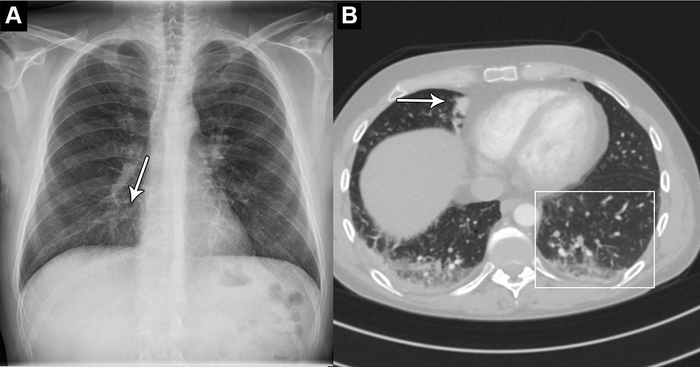

image: Images in a 44-year-old man who presented with chest pain and dyspnea. (A) Chest X-ray shows very subtle nodular opacities, primarily in lower lobes, representative of pneumonia and a discrete silhouette sign of the right cardiac border (arrow). The AI system interpreted this chest X-ray as normal. It was also interpreted as normal in the clinical radiology report. (B) CT scan shows the lower lobe airspace opacities with vague tree-in-bud morphology (box) and an area of consolidation (arrow). Pulmonary angiography was performed 5 hours after X-ray. This was the sole false-negative “critical” finding by the AI tool. view more